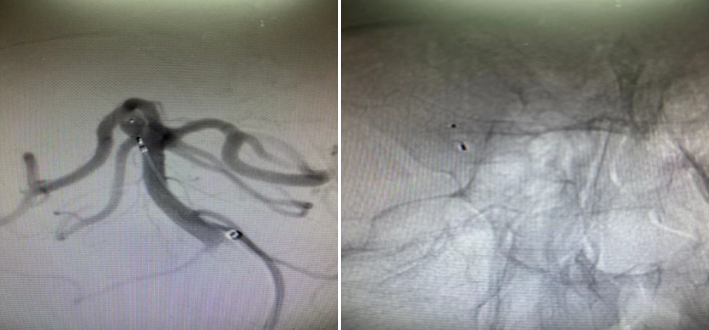

患者28岁,因反复头痛头晕在当地医院检查提示基底动脉顶端动脉瘤。患者患有高血压,基底动脉动脉瘤随时可能破裂致自发颅内出血,严重时可能致残致死。因该位置手术风险较大,地州医院无法手术,于是患者辗转来到亚洲色吧 附二院神经外科一病区。入院后,神经外科一病区为患者行全脑血管造影,提示右侧小脑上动脉动脉瘤。

该动脉瘤位于右侧小脑上动脉及大脑后动脉之间,宽颈,常规栓塞较为困难,支架置入难度较大,若置入支架辅助栓塞,后期患者需抗凝抗血小板治疗较长时间;开颅手术夹闭则创伤较大,恢复时间较长。蒲军主任在仔细阅读患者DSA造影资料后,提出可行现最新的自膨式瘤内栓塞系统治疗该动脉瘤,在告知家属病情及相关情况后,患者家属同意行该手术。

经过周密的术前检查,在蒲军主任的指导下,黄晓斌及张明副主任医师、王和平博士团队顺利为患者实施了自膨式栓塞系统小脑上动脉动脉瘤栓塞手术。手术时间20分钟,完整填塞动脉瘤,术后造影提示动脉瘤未显影,周围各支重要血管血流正常。术后,患者恢复良好,无任何神经功能障碍,无需服用任何特殊药物,并于3天后出院。